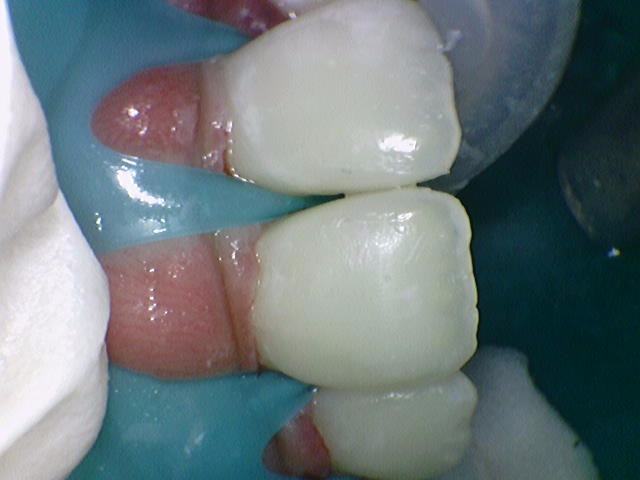

앞니 사이에 썩은 충치들.😥 치료 중.

치료 후. 깨끗하게 레진으로 사이 충치 치료 완료👍